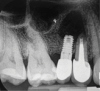

Report of a case. A 45-year-old male patient was referred with pain, redness, and swelling around an implant in the position of the maxillary right second premolar. The implant had been in clinical function for 3 years. The patient had a history of endodontic treatment and tooth loss and subsequent implant treatment in the region. Radiographic examination showed a radiolucency around the apical portion of the implant and the adjacent tooth. The implant was clinically stable and the neighboring tooth No. 4 was considered to have a periapical lesion. Initially, the patient received antibiotics (clindamycin 300 mg, three times daily) and was followed up for 2 weeks. After this, the patient was scheduled for surgical exploration of the implant area. Treatment comprised elevation of a full-thickness flap, curettage of the apical lesion, irrigation with saline, and removal of the apical portion of the implant and apicoectomy of the adjacent tooth (Figure 3 and Figure 4), including a guided bone regeneration (GBR) procedure with a cancellous particulate allograft and 20 mm x 30 mm pericardium membrane. Granulation tissue was sent for histopathology analysis, which revealed a periapical inflammatory infection. At the 4-month follow-up increased radiographic bone density could be observed consistent with the formation of bone not only around the implant apex but also along the root of tooth No. 5 (Figure 5).

Fig 5. Postoperative radiograph showing defect ossification after 4 months.

Figure 5